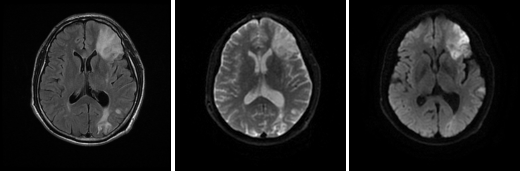

病例一 男,53歲, 突發(fā)右側(cè)肢體力弱, 言語(yǔ)不清, 伴惡心嘔吐、 伴頭暈頭昏、 伴視力模糊, 無(wú) 意識(shí)障礙、 無(wú)面癱。

CBT CBV MTT DLY TTP

從圖中CTA可見(jiàn)左側(cè)大腦中動(dòng)脈M 1段閉塞。

腦灌注所示左側(cè)大腦中動(dòng)脈供血區(qū)DLY、 TTP、 MTT時(shí)間顯著延長(zhǎng),CBF略減低, 考慮為 急性腦梗死; 左側(cè)額葉、 頂枕葉CBF、 CBV顯著減低, 符合軟化灶表現(xiàn)。

經(jīng)大動(dòng)脈腦血管造影+機(jī)械血栓清除+動(dòng)脈內(nèi)溶栓術(shù), 顯示血管病變位置與CTA顯示病變 位置相符, 治療后, 該血管供血區(qū)域得到明顯改善。

核磁共振檢查證實(shí)梗死核心區(qū)域與灌注圖所示區(qū)域匹配。